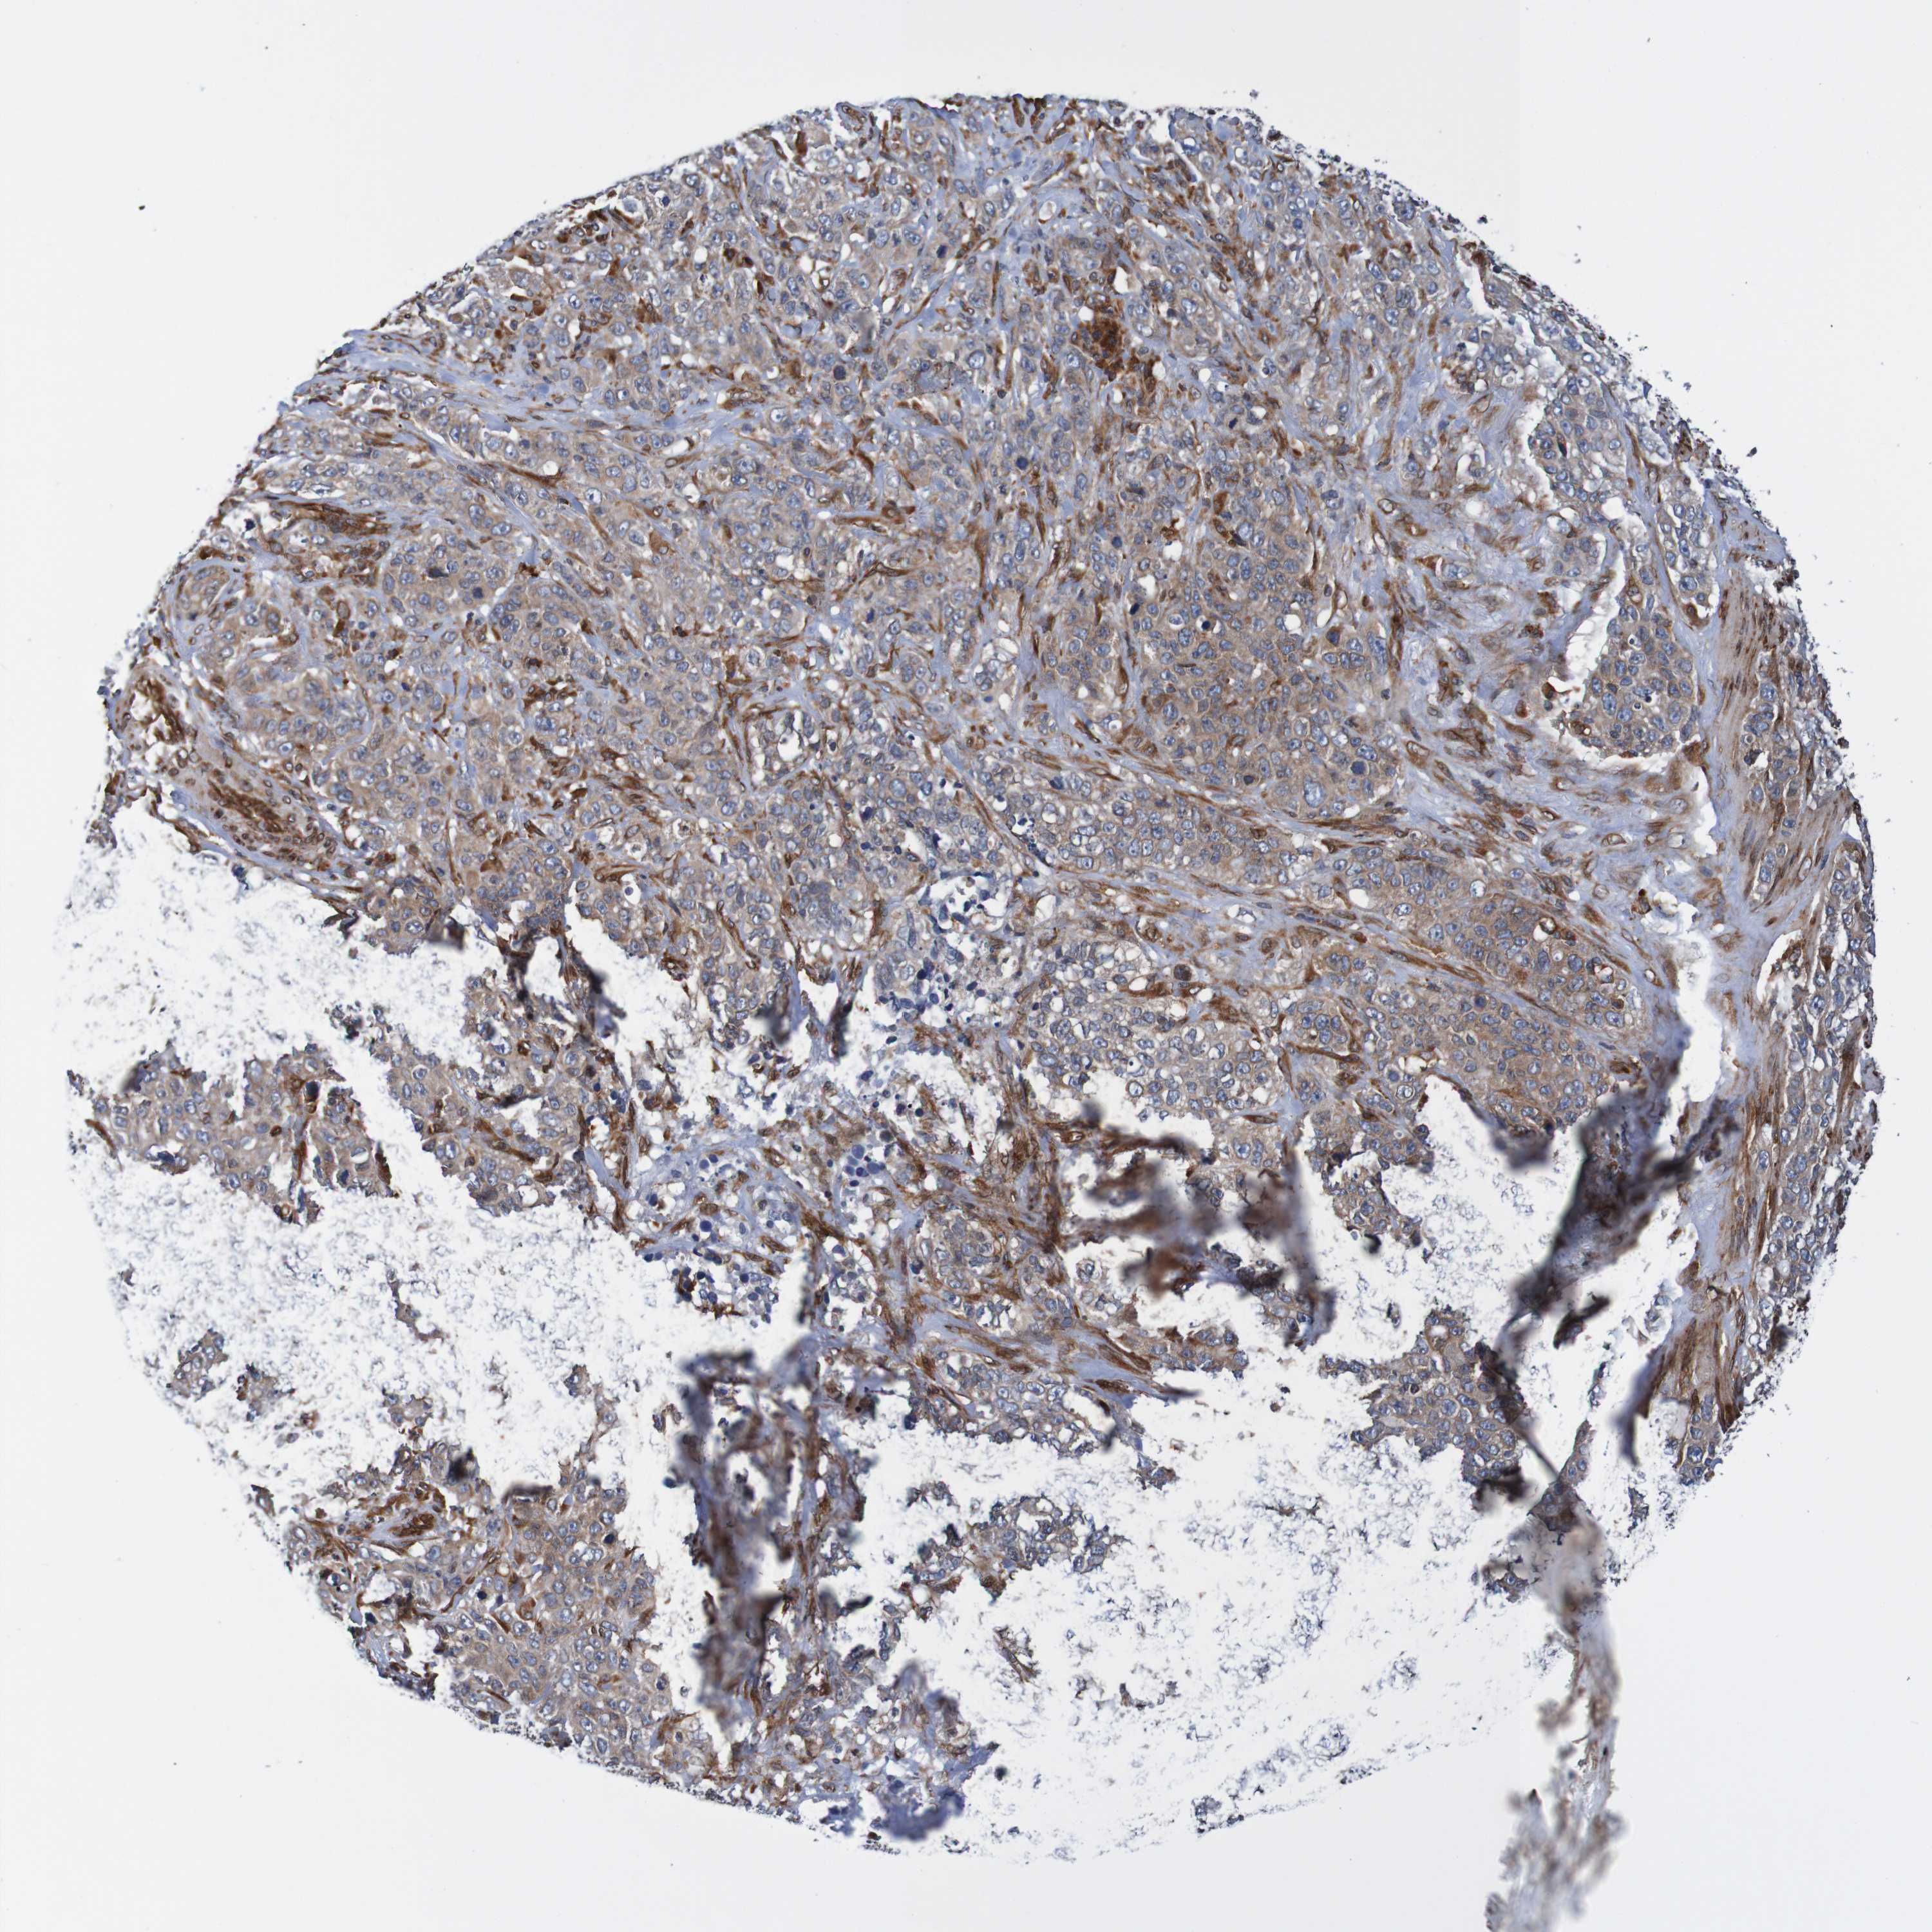

STOMACH CANCER - Protein expressioni

A mouse-over function shows sample information and annotation data. Click on an image to view it in a full screen mode. Samples can be filtered based on level of antibody staining by selecting one or several of the following categories: high, medium, low and not detected. The assay and annotation is described here.

Note that samples used for immunohistochemistry by the Human Protein Atlas do not correspond to samples in the TCGA dataset.

Antibody stainingi

Antibody staining in the annotated cell types in the current human tissue is reported as not detected, low, medium, or high, based on conventional immunohistochemistry profiling in selected tissues. This score is based on the combination of the staining intensity and fraction of stained cells.

Each image is clickable and will lead to virtual microscopy that enables deeper exploration of all samples and also displays staining intensity scores, fraction scores and subcellular localization as well as patient and tissue information for each sample.

Antibody HPA011785

Staining

High

Medium

Low

Not detected

Intensity

Strong

Moderate

Weak

Negative

Quantity

>75%

75%-25%

<25%

None

Location

Nuclear

Cytoplasmic/membranous

Cytoplasmic/membranous,nuclear

Adenocarcinoma, NOS

Adenocarcinoma, High grade